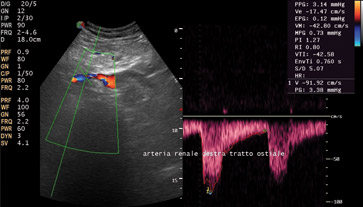

Con l’ecocolordoppler a tutto ciò viene aggiunta la visualizzazione del flusso ematico all’interno dei principali vasi sanguigni. Tale visualizzazione viene assunta attraverso il collegamento in tempo reale di una immagine ecografica bidimensionale con un segnale doppler pulsato. L’ecocolordoppler è indicato per ilmonitoraggio e la diagnostica delle stenosi arteriose e venose, degli aneurismi, delle trombosi e delle insufficienze venose.